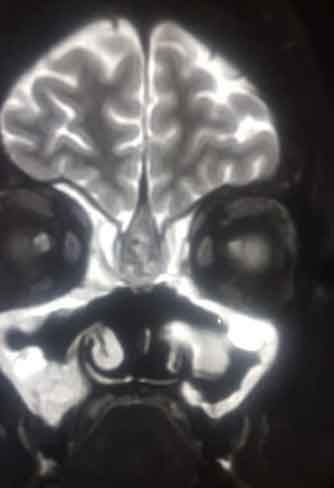

These may arise from the nose or from any of the adjoining sinuses. Their symptoms include nasal obstruction, bleeding, etc. These tumours can be very challenging to manage because of their approximation to various vital structures like nerves, blood vessels, eye, brain, etc. We provide the option of open as well as endoscopic removal of these tumours.